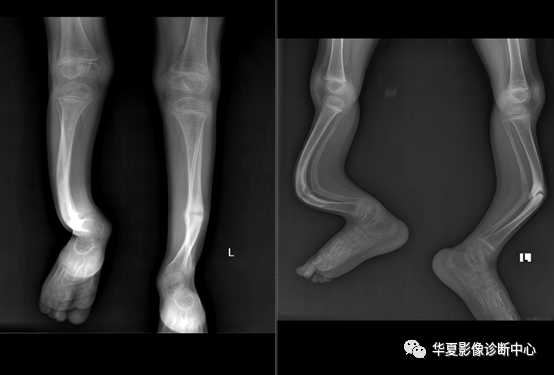

四、X线表现

(1)胫骨中下1/3交界处有假关节存在,假关节两端呈锥形,中间骨质吸收与消失,骨质细长,皮质板薄,腓骨有时出现同样改变。(2)胫骨中下1/3交界处有胫骨前弓,骨皮质增厚,骨髓腔纤维化,胫骨较短,髓腔内有囊性改变,腓骨可正常。(3)胫骨自后向外成角,较短,骨质变粗,髓腔可无变化。